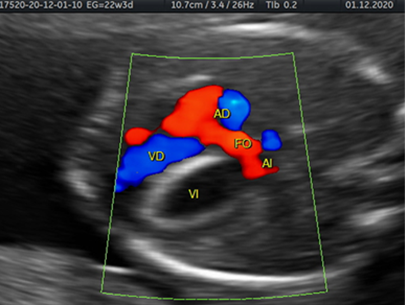

El endocardio experimenta una transición a fibroblastos y produce colágeno-elastina, esta transición y producción de colágeno-elastina se da en la vida intrauterina y en la infancia, cuando el potencial de crecimiento celular sea mayor.. Es por esto que la fibroelastosis endocárdica se caracteriza por una pérdida total de la contractibilidad del ventrículo izquierdo, debido a un desarrollo insuficiente de la musculatura cardiaca y formación de tejido fibroso anormal, condicionando así una severa disfunción contráctil, asociado o no a una estenosis aórtica (Figura 2).

Esta patología puede estar asociada también a otras anomalías genéticas como tales como el síndrome de Turner, el síndrome de Jacobsen y la trisomía 13 y 18 8.

Los hallazgos ecográficos, en el caso de fibroelastosis del ventrículo izquierdo, muestran las paredes de este dilatadas e hiperecogénicas, en caso de estenosis aórtica la válvula aórtica aparenta estar engrosada, con dilatación postestenótica. Su diagnóstico definitivo se realiza mediante la biopsia del ventrículo izquierdo 9.